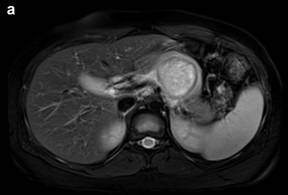

DW-MRI (Figure 4a) was performed (using b values of 50, 400 and 800) and the mean apparent diffusion coefficient (ADC) map was calculated (Figure 4b). The lesion presented a relatively high ADC value (1.8 x10-3 mm2/sec) compared to the ADC of the normal pancreatic gland (1.4 x10-3 mm2/sec), although there were some intralesional small areas of relatively low signal (minimum values of 1.3 x10-3 mm2/sec). T2/DW fusion imaging was performed (Figure 4c). Gadolinium-enhanced MR imaging (Figure 5) showed early peripheral enhancement of the fibrous pseudocapsule. No central contrast enhancement was observed.

Figure 4. a. Axial diffusion-weighted image (b value of 800 sec/mm2) shows a lesion with low signal intensity with some small central areas of higher signal intensity from restricted diffusion. b. Apparent diffusion coefficient mean value of the lesion is 1.8x10-3 mm2/sec with the central hypointense areas having a minimum value of 1.3x10-3 mm2/sec (arrows). c. T2-weighted and diffusion-weighted imaging were fused displaying a colored map of abnormal diffusion parameters. |

The most common enhancement pattern of solid pseudopapillary tumor consists of early, peripheral enhancement of the tumoral pseudocapsule during the arterial phase, compared with the normal pancreas and the lesion itself [4, 5]. In some cases there is a progressive but heterogeneous fill-in of the lesion during the portal venous and equilibrium phases [5], showing less enhancement that the adjacent normal pancreas [4] consistent with a hypovascular tumor.

Our case report specifically illustrates the potential of DW-MRI findings in solid pseudopapillary neoplasms in pediatric patients. Wang et al. [8] describe DW-MRI in pancreatic lesions in adult patients and suggest that the components of the neoplasm (solid, cystic or hemorrhagic) determines the degree of diffusion and the ADC values, with the solid components accounting for the relatively low ADC values. In our case multiple b value DW-MRI allowed to discriminate better than T2-weighted or contrast-enhanced series the different components of the lesion according to signal behavior along with the increase in b value. Areas with low ADC values (compared to both normal pancreas and necrotic areas of the lesion) correspond probably to areas of increased cellularity. There are few reports about DW-MRI in cystic pancreatic neoplasms [8], so it remains to be established the role of DW-MRI to discriminate between benign and malignant lesions. Nevertheless, our findings emphasize the potential of DW-MRI to substitute contrast-enhanced imaging, particularly in the pediatric population.